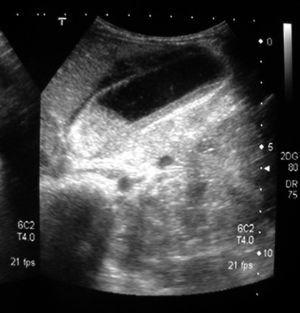

Se trata de un lactante sano de 11 meses que en los últimos 15-20 días presenta episodios de diarrea que alternan con estreñimiento, junto con decaimiento, falta de vitalidad, rechazo del alimento y de forma esporádica vómitos acuosos (no biliosos) y alimenticios. Acude por empeoramiento del estado general, distensión abdominal con dolor a la palpación, pérdida ponderal de 1,5 kg junto con deposiciones diarreicas, líquidas, amarillentas y grumosas, sin moco ni sangre. En la exploración física pesó 8.100 g (P3), con un regular estado general, afebril, decaído y quejumbroso. Pelo rubio ralo, palidez cutánea, ausencia de lágrimas, saliva espesa y lengua geográfica. No presentaba edemas ni adenopatías. El abdomen estaba distendido, doloroso a la palpación profunda y superficial, sin visceromegalias y con buen peristaltismo, la ampolla rectal estaba vacía aunque al realizar un tacto salieron heces líquidas a chorro y luego grumosas, amarillentas, sin moco ni sangre. Exámenes complementarios: Hemograma: 30.500 leucocitos/μl (57 % neutrófilos, 33 % linfocitos, 2,5 % monocitos, 7,5 % eosinófilos). PCR: 349 mg/l, colesterol total: 99 mg/dl, bilirrubina total: 1,16 mg/dl (directa: 0,39 mg/dl), GOT: 43 U/l, GPT: 39 U/l, proteínas totales: 5 g/dl. Creatinina, urea, amilasa, iones e IgA normales. Anticuerpos antiendomisio (+1/160), antitransglutaminasa (75 U/ml) y antigliadina (42,2 mg/l) elevados. La radiología simple de abdomen no presentó alteraciones pero en la ecografía (fig. 1) se apreció una vesícula biliar distendida con paredes engrosadas (6 mm) y con microlitiasis, barro biliar, productos de infección y litiasis de 1 cm a nivel del cuello; parénquima hepático vecino a la vesícula hipoecogénico por edema y vía biliar no dilatada. Todo ello sugestivo de colecistitis aguda litiásica. El empeoramiento del estado general obligó a su traslado a cirugía infantil donde se mantuvo una actitud conservadora con tratamiento antibiótico intravenoso que resolvió el proceso agudo. Días después la biopsia yeyunal mostró atrofia vellositaria subtotal. Tras el alta el paciente ha presentado una excelente nutrición con dieta exenta de gluten y en las repetidas ecografías abdominales, siempre en ayunas, nunca se ha visualizado la vesícula biliar (vesícula excluida).

Figura 1. Ecografía abdominal. Vesícula biliar dilatada con barro biliar en su interior.